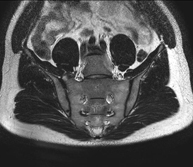

Prova diagnòstica no invasiva que consisteix en l'obtenció d'imatges d'alta definició anatòmica de la pelvis mitjançant l'ús d'un camp electromagnètic i ones de ràdio (amb un emissor i un receptor). No utilitza radiació ionitzant. Es realitza per a l'estudi de patologies d'úter, d'ovari, de trompes i de vagina, ja siguin d'origen tumoral, inflamatori o vascular. També permet valorar les estructures adjacents localitzades a la pelvis i la identificació de les seves alteracions. De vegades és necessari l'ús de contrast intravenós (Gadolini) per caracteritzar les lesions. - RM Pelvis masculina

Prova diagnòstica no invasiva que consisteix en l'obtenció d'imatges d'alta definició anatòmica de la pelvis masculina mitjançant l'ús d'un camp electromagnètic i ones de ràdio (amb un emissor i un receptor). No utilitza radiació ionitzant. No requereix preparació prèvia. En algunes ocasions necessita l'ús de contrast paramagnètic (Gadolini) per caracteritzar les lesions. Aquesta prova permet valorar òrgans com la bufeta urinària, la unió entre els urèters i la bufeta, la pròstata, les vesícules seminals, la uretra i els ossos de la pelvis, entre d'altres. - RM de Fetge